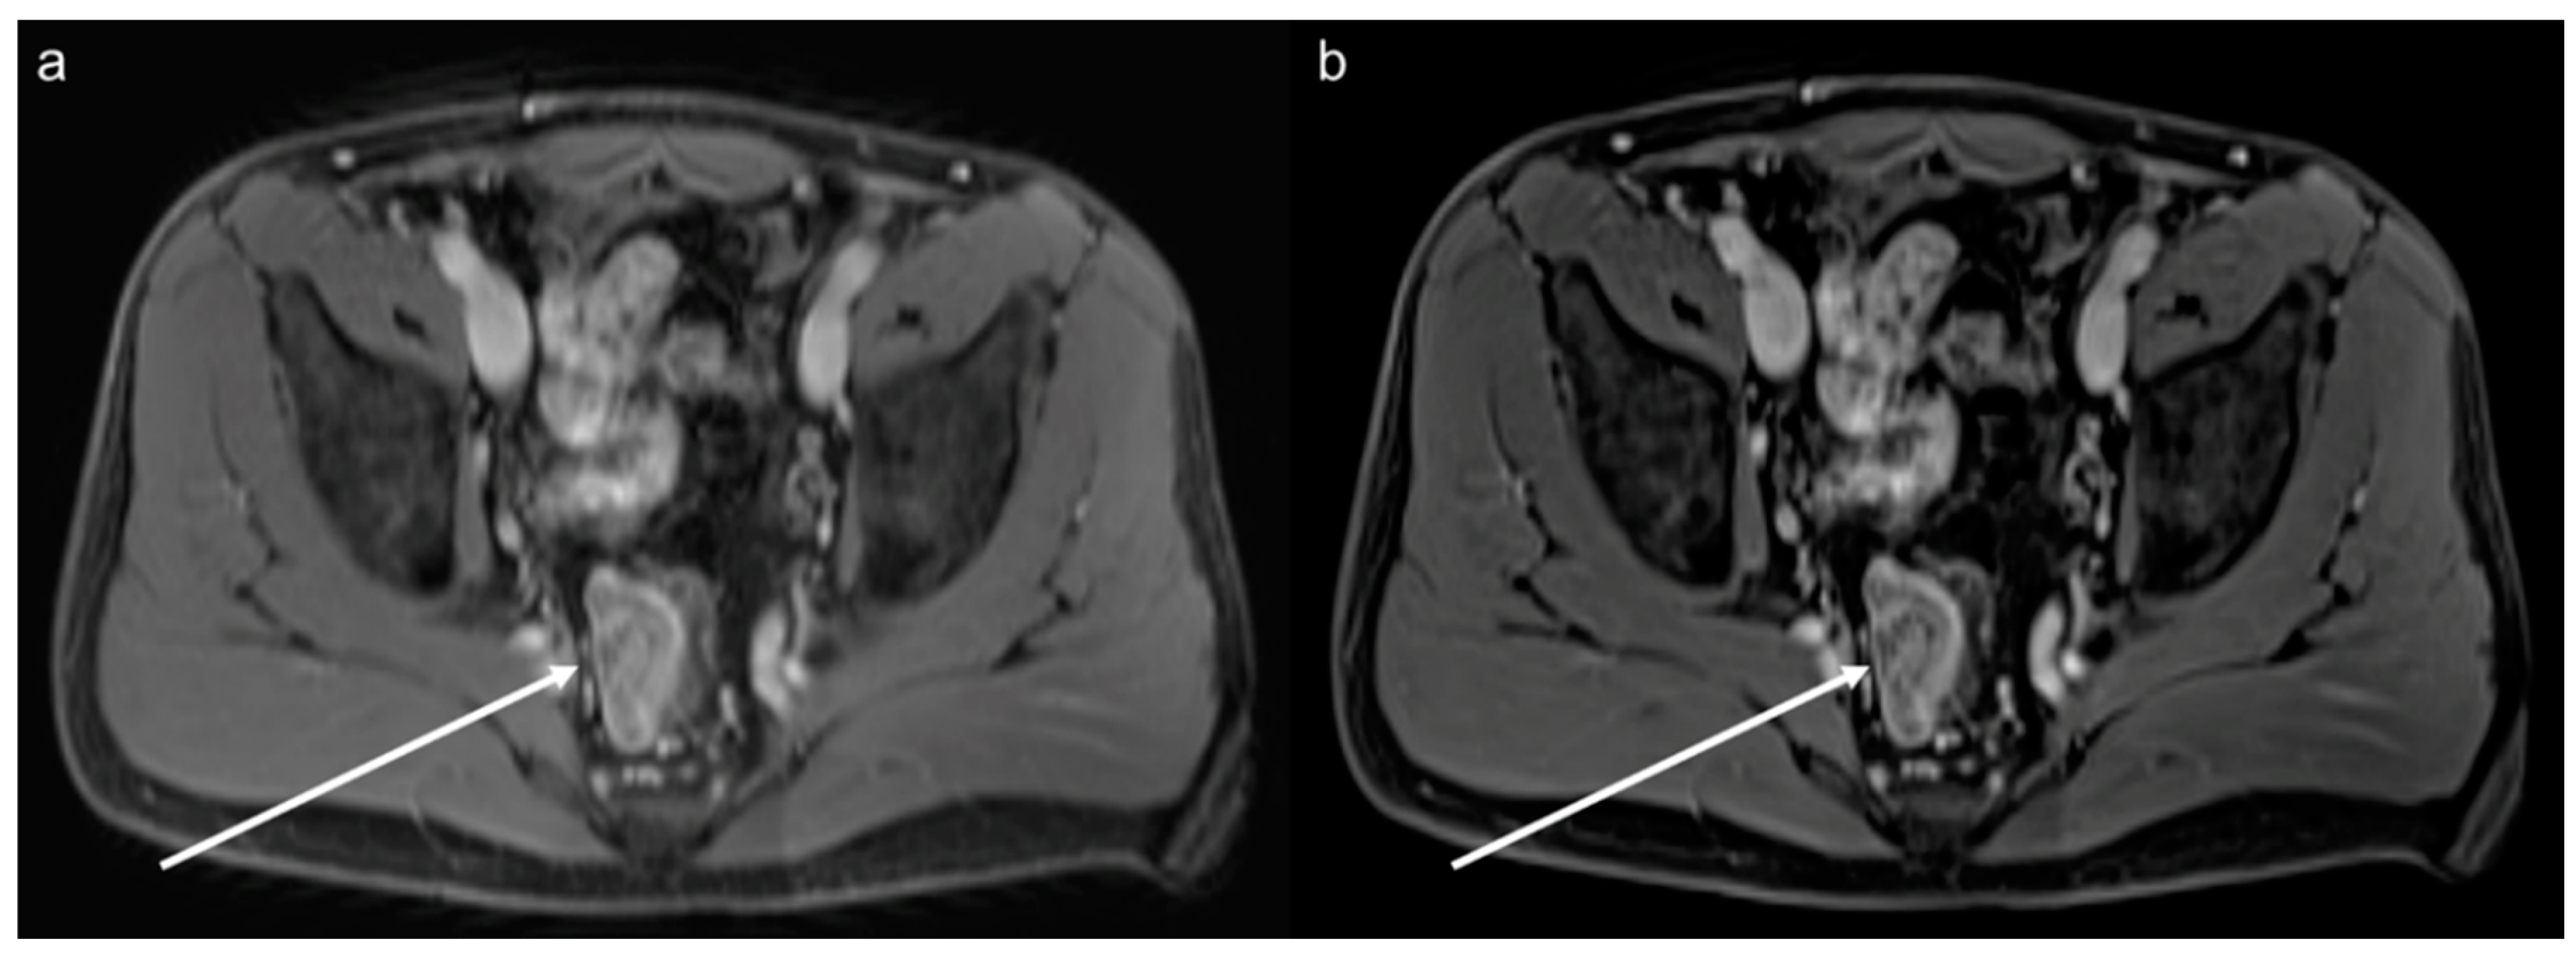

3.5. Lesion Assessment

3.6. Acquisition Time